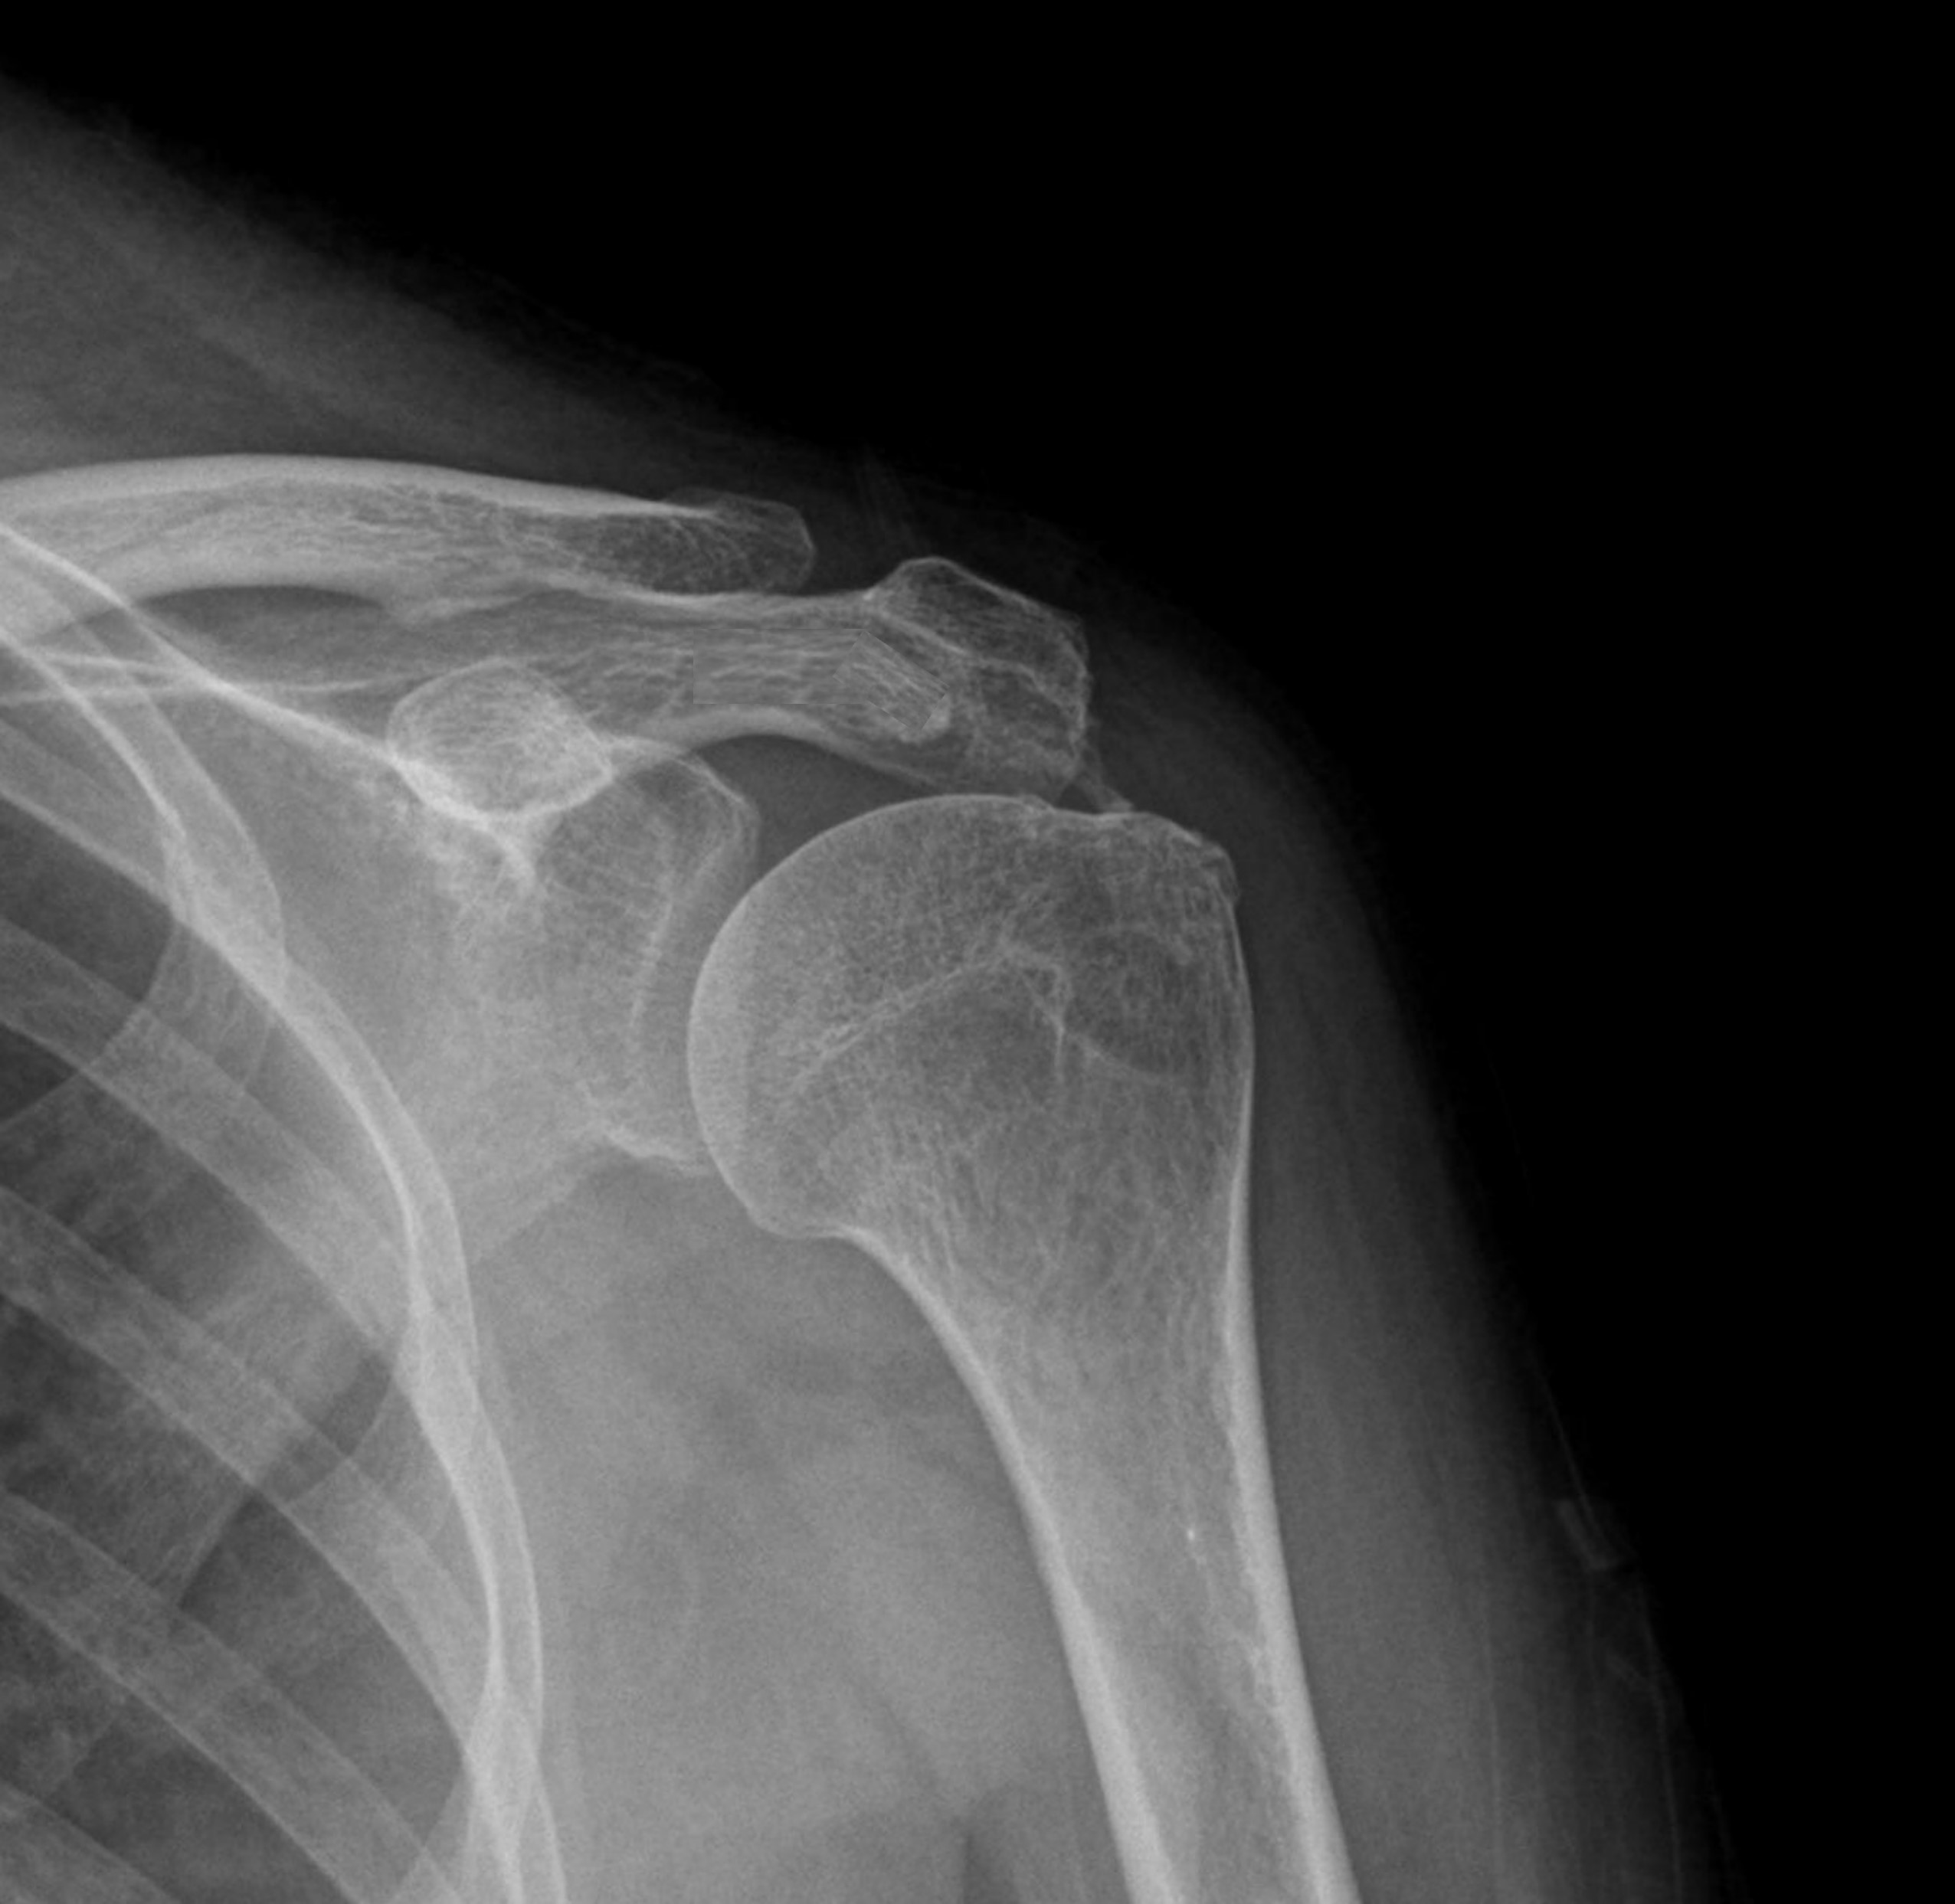

케이스 2: 휴지기 중형 석회 (1회 제거)

환자: 40대 여성, 좌측 어깨 야간통 1년

시술 전:

약 1.2cm 석회, 휴지기

충격파 10회 + 주사흡입술 2회 받았으나 호전 없음

시술 후:

1회 분쇄흡입술로 제거

야간통 소실, 수면 가능해짐